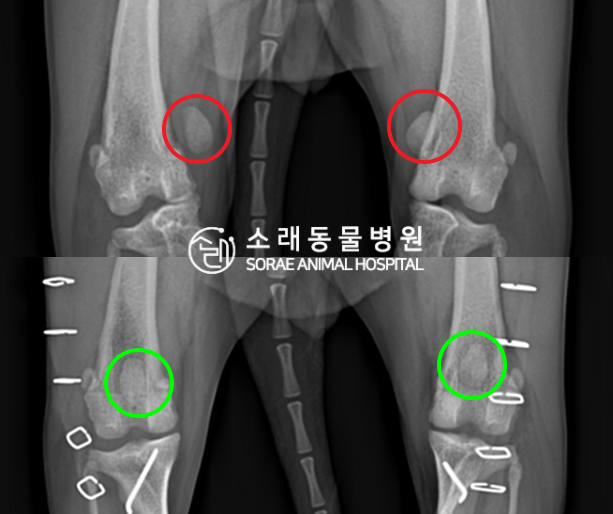

수술전과 수술후에 촬영한 소금이의 슬개골

방사선 사진입니다. 나란히 놓고 비교해보니

슬개골의 위치에 확연한 차이가 있는 것을

확인해 볼 수 있는데요. 내측으로 탈구되어 있던

슬개골이 원래 제자리인 활차구에 예쁘게

자리 잡고 있는 모습을 확인할 수 있었습니다.